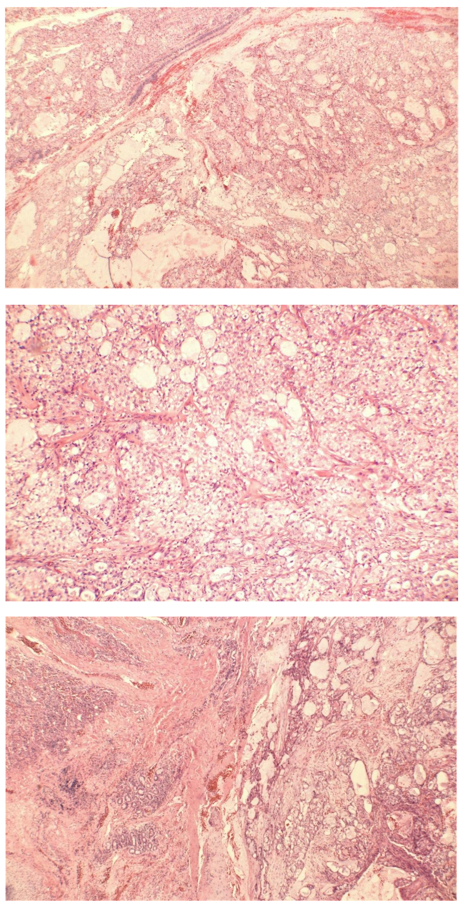

Histopathological examination revealed low-grade bronchial mucoepidermoid carcinoma (Figure 4a,4b,4c). It showed a malignant epithelial neoplasm composed predominantly of invasive carcinoma with focal squamous differentiation and mucin-secreting cells, set within a background of cystic spaces and focal solid areas. A small high-grade component, comprising less than 10% of the overall tumor volume, demonstrated solid and nested architecture, cytological atypia, increased mitotic activity, necrosis, and hemorrhage (Figure 4).

Immunohistochemical analysis showed the tumor cells were positive for Pan-Cytokeratin (Pan-CK), Cytokeratin 7 (CK7), and focally positive for CK5/6 and p63 [5]. The tumor cells were negative for TTF-1, Napsin A, Synaptophysin, Chromogranin, CD56, CD10, GATA-3, p16, Melan-A, S100, and Progesterone Receptor (PR). Mucicarmine stain highlighted the mucin-secreting component. The Ki-67 proliferation index was approximately 4%. The histomorphological features, together with the immunohistochemical profile, support a diagnosis of low-grade mucoepidermoid carcinoma, likely originating from bronchial submucosal glands, with a focal high-grade component (<10%). Hilar lymph node biopsy showed no evidence of LN involvement.

Figure 4: Hematoxylin and Eosin stain histopathology showing:

(a) mucous filled glands adjacent to respiratory epithelium (left) (X10)

(b) mucus secreting cells, squamoid cells without significant keratinization, and intermediate type cells (X40)

(c) mucous filled glands adjacent to lung parenchyma (X10)